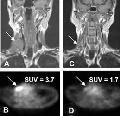

图注:A为1例患者MR影像,箭头所指处示右侧颈部淋巴结肿大;B为横断面PET影像,可见FDG呈高密度报入;C示2个周期化疗后淋巴结缩小至正常;D示2个周期化疗后肿瘤组织摄入FDG的量减少。

结果显示,治疗前肿瘤有很高的FDG摄取值,20例患者中有10例在化疗结束时达到完全缓解,其余10例未缓解。在10例缓解的患者中,有4例持续缓解(无进展生存时间为24~34个月),其余6例复发(无进展生存时间为8~16个月)。在预测24个月时临床转归方面,PET分析显示出很高的敏感性(87.5%)和准确性(80%),但特异性较低,只有50%。缓解的患者在治疗1~2个疗程后SUV较治疗前显著降低,而未缓解患者治疗前后SUV的变化不如缓解患者明显(差异显著)。除此之外,以SUV降低60%作为判断标准,可以将缓解的患者与未缓解患者明确区分开。